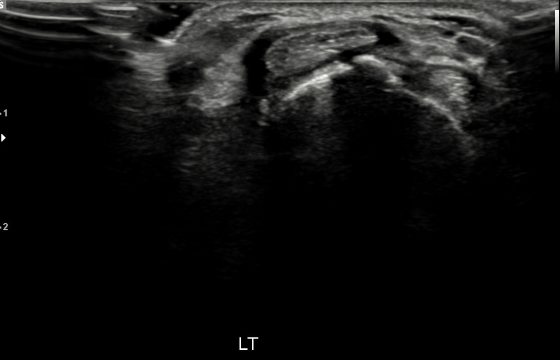

손목건초염 수술 후 초음파 사진

2021.10.02

염증 조직으로 힘줄이 조여있는 모습 (검은색 부분)